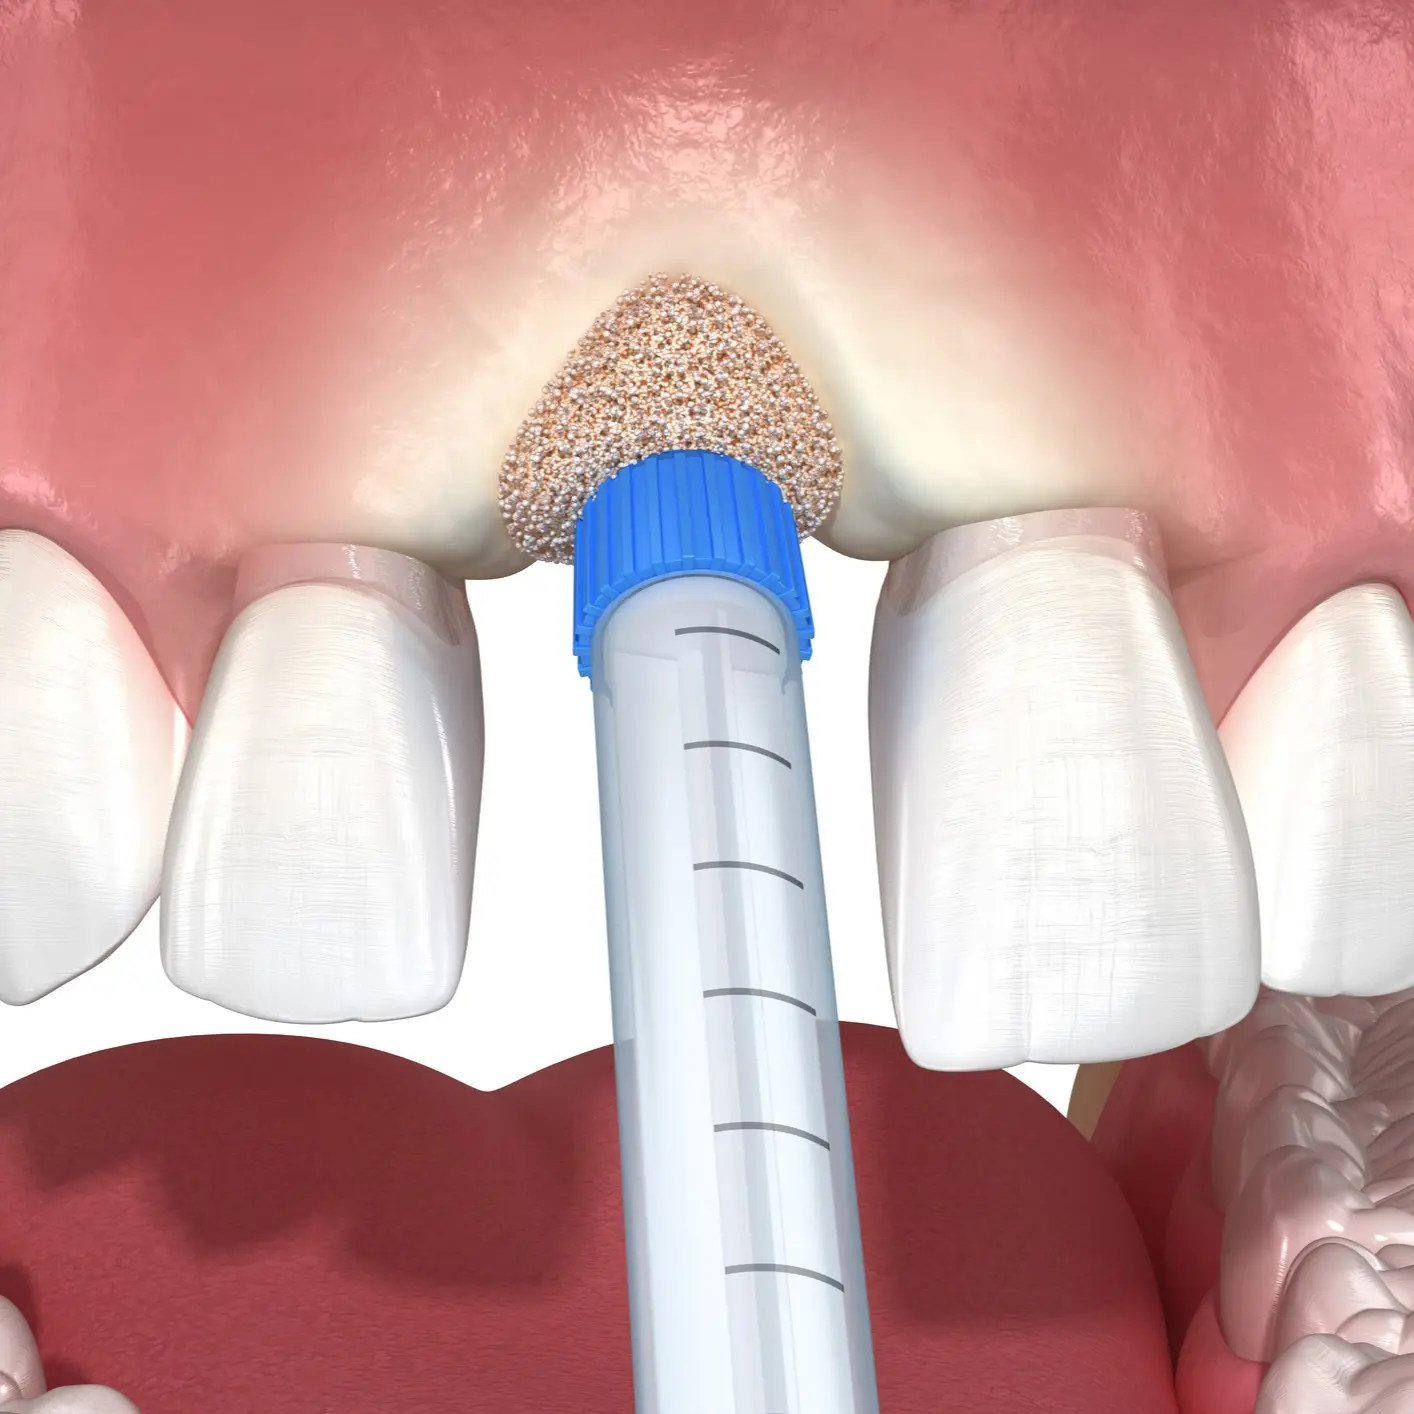

Bone Grafting is a surgery that rebuilds or strengthens bone. In dentistry, doctors restore jawbone lost from gum disease, injury, or tooth extraction. A strong jawbone is often needed for dental implants, and this treatment creates the solid base required for lasting results.

Surgeons may take bone from the patient, use donor tissue, or place synthetic material. The graft stimulates new bone growth, which improves strength and stability. Doctors also perform Bone Grafting in orthopedic surgery to support healing after fractures or joint operations. This procedure reduces pain, restores function, and prepares patients for advanced restorative care.